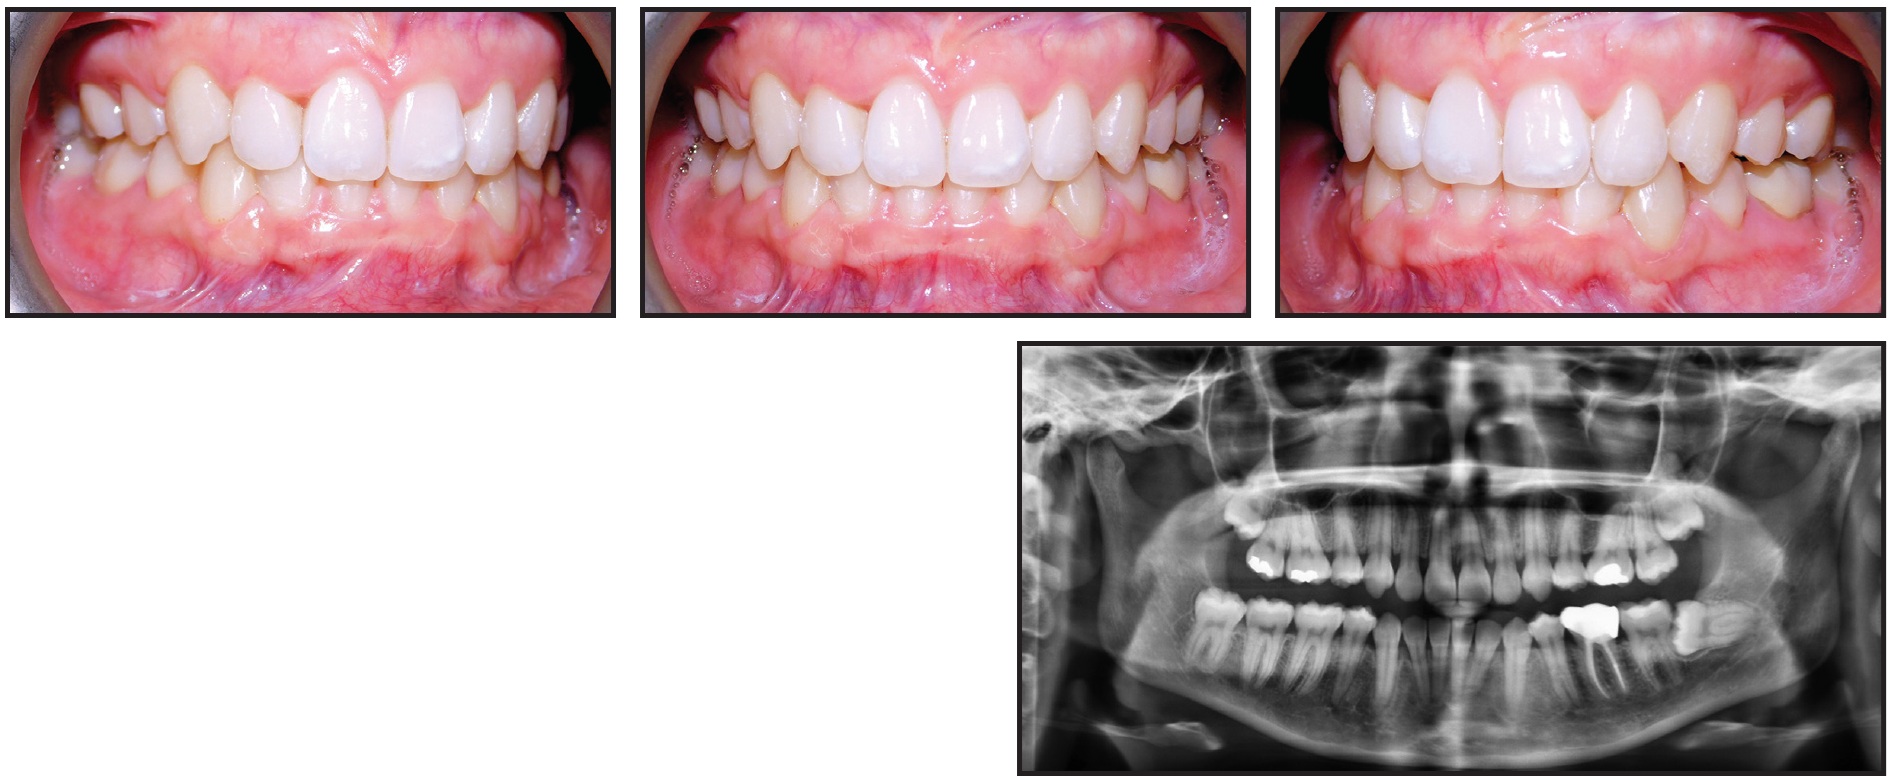

A late-teen patient was undergoing orthodontic treatment to set up for a Le Fort surgical advancement and downgraft. The completed surgical setup was held in place with elastic chain (Fig. 18). For patient comfort, I waited to place surgical lugs and final stainless steel ligatures until a day or two prior to surgery.

The surgeons and I completed our virtual planning, but because of the COVID-19 pandemic, we were unable to schedule an operating room until three months after the records were taken. When the patient returned to me, two days before surgery, considerable maxillary spacing had opened (Fig. 19). Oops!

Fig. 18 Elastic chain used to retain completed orthodontic setup of late-teen patient for Le Fort surgical advancement and downgraft.

Fig. 19 Patient two days before surgery, with considerable maxillary space opening (note new surgical lugs and stainless steel ligatures).

I immediately called the surgeons, and after assessing the impact on our plan, we decided to press on with the surgery. I made impressions for our reference and attached surgical lugs and stainless steel ligatures. Two amazing oral surgeons, Drs. Dan Schlieder and Corey Toscano, were able to complete the surgery and fabricate new surgical splints during the procedure. Although the patient, family, and team were pleased with the outcome, we would have preferred not having to scramble at the last minute.

This mistake could have been avoided by placing standard stainless steel ligatures under the archwire once the spaces had been closed. My advice can be applied in many situations, but especially when trying to stabilize a decompensated patient, in whom all the soft tissue is fighting against the presurgical dental decompensations.